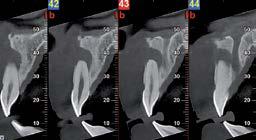

Nell’ambito della radiologia 3D ortopedica, il centro diagnostico utilizza il nuovissimo macchinario NewTom 5G XL, in grado di individuare con la massima precisione la presenza di fratture o lussazioni delle articolazioni, controllare la corretta guarigione di una frattura, valutare una lesione o una ferita causata da infezione, artrite o crescita anormale dell’osso.

Il tutto mediante una semplice e veloce scansione, grazie alla quale si otterranno diverse immagini in 3D ad altissima risoluzione e, per ottenere immagini ancora più nitide mediante un bassissimo dosaggio di radiazioni, gli esperti si avvalgono dell’innovazione racchiusa nella tecnologia Cone Beam.

Se con la radiologia tradizionale era necessario eseguire scansioni multiple, la novità introdotta dal macchinario NewTom 5G XL risiede nella capacità di fornire immagini ad alta risoluzione in un’unica scansione, mostrando nitidamente i dettagli delle articolazioni degli arti superiori e inferiori. Inoltre, a differenza della tecnologia 2D, la radiologia 3D ortopedica permette di individuare immediatamente alcune patologie come quella del metatarso, la quale richiede un allineamento visivo dedicato o una diagnosi delle micro fratture ossee.